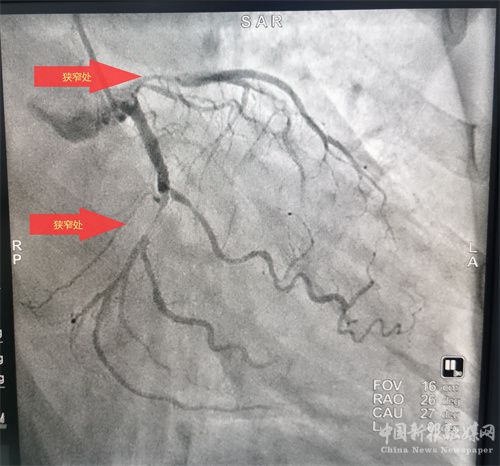

術(shù)前

患者溶栓成功后,經(jīng)患者及家屬同意后行冠狀動脈造影檢查,患者冠脈顯示前降支次全閉、回旋支狹窄95%、右冠近端狹窄85%,病情緊急,李維軍、楊亮主任向家屬詳細(xì)講明病情后,予以開通前降支和回旋支,植入支架3枚。手術(shù)全程用時不到一個小時。目前,患者病情穩(wěn)定。